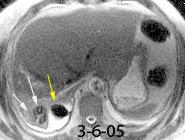

Marzo 2014: Perforación longitudinal distal secundaria a episodio de vómito (síndrome de Boerhaave). Derrame pleural izdo. que evoluciona a empiema.